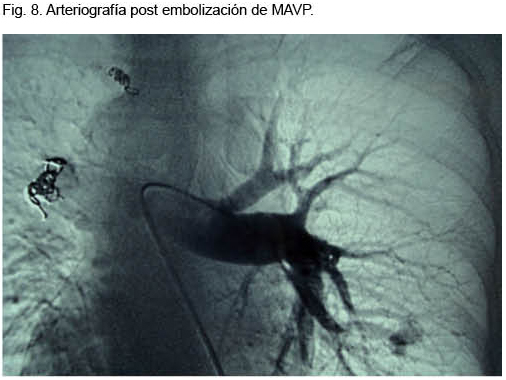

Se destacaba la existencia de múltiples telangiectasias mucocutáneas (Figura 6). Se realizó angioTC que confirmó el diagnóstico de MAVP múltiples (Figura 7); dos a nivel de lóbulo superior izquierdo y otra a nivel de lóbulo inferior derecho. Se realizó arteriografía y, simultáneamente, la embolización de las dos MAVP izquierdas, quedando una malformación a nivel del lóbulo inferior derecho simple de 3 mm (Figura 8).

En cuanto a los métodos de diagnóstico utilizados en los tres casos, debemos de jerarquizar que la RxTx fue patológica en todos; ésta es anormal en el 98% de los casos(2). La gasometría arterial ventilando espontáneamente al aire confirmó la presencia de insuficiencia respiratoria crónica tipo I en los tres casos, y sin corrección luego de la administración de oxígeno por 30 minutos, permitiendo afirmar el mecanismo de shunt. En el caso número 1 también se destacaba clínicamente la presencia de platipnea y ortodeoxia. La angio TC fue el método de diagnóstico en los tres casos, con un excelente rendimiento. Se trata de una técnica sensible, de bajo costo, que permite establecer el diagnóstico de MAVP. Permite la valoración del tamaño, topografía y angioarquitectura, así como el seguimiento de la lesión luego de realizado tratamiento(5). En los tres casos la confirmación diagnóstica fue mediante la angioTC, permitiendo realizar la arteriografía sólo con una finalidad terapéutica. Los tres pacientes fueron sometidos a embolización con coils fibrilares de platino, con excelente evolución clínica. Su objetivo es la oclusión de la arteria aferente (única o múltiple) con el fin de excluir la comunicación arteriovenosa patológica, preservando el máximo posible de parénquima funcionante. Las indicaciones de tratamiento se fundamentan en la elevada morbimortalidad histórica de estos pacientes. Fundamentalmente debido a complicaciones neurológicas, las cuales se observan hasta en 30% de los pacientes no tratados. A esto debemos sumarle las importantes secuelas neurológicas, muchas de ellas invalidantes, a las cuales quedan expuestos. A su vez, los mismos autores reportaron un riesgo de padecer un “stroke” de 1,5% por año si la MAVP presenta una arteria aferente con un diámetro igual o mayor de 3 mm(2-9). Los materiales más utilizados en la actualidad para la embolización son los coils(1-8) y los tapones vasculares(10,11). Los coils son espirales metálicas, expansibles, de diferentes diámetros y longitudes, según el vaso o estructura a tratar y que, por lo general, se encuentran recubiertos de fibras artificiales que aumentan su potencial trombogénico(12).

El tapón vascular de Amplazer es un dispositivo cilíndrico, autoexpansible, confeccionado con una malla metálica de alambre(10,11). Éste permite una oclusión más precisa y su posición puede verificarse antes de ser liberado; si ésta no es satisfactoria, se puede recolocar o retirar. Asimismo puede ser utilizado tanto en embolizaciones arteriales como venosas, presenta un menor riesgo de migración, se libera fácilmente y permite producir una oclusión completa con un solo dispositivo. De esta manera se disminuye el tiempo de embolización así como su costo en fístulas grandes(10,11). Los tres pacientes fueron sometidos a embolizacion con coils fibrilares de platino con excelente evolución clínica. Los casos 1 y 3 requirieron un segundo procedimiento en la evolución por haber alcanzado el tiempo máximo de contraste y presentar múltiples MAVP. Los efectos adversos presentados fueron menores, e incluyeron dolor torácico, tipo puntada de lado, las primeras 24 hs, de fácil control con antiinflamatorios no esteroideos. La mejoría sintomática y fisiopatológica de la insuficiencia respiratoria fue inmediata en todos los casos, objetivada mediante gasometría arterial.